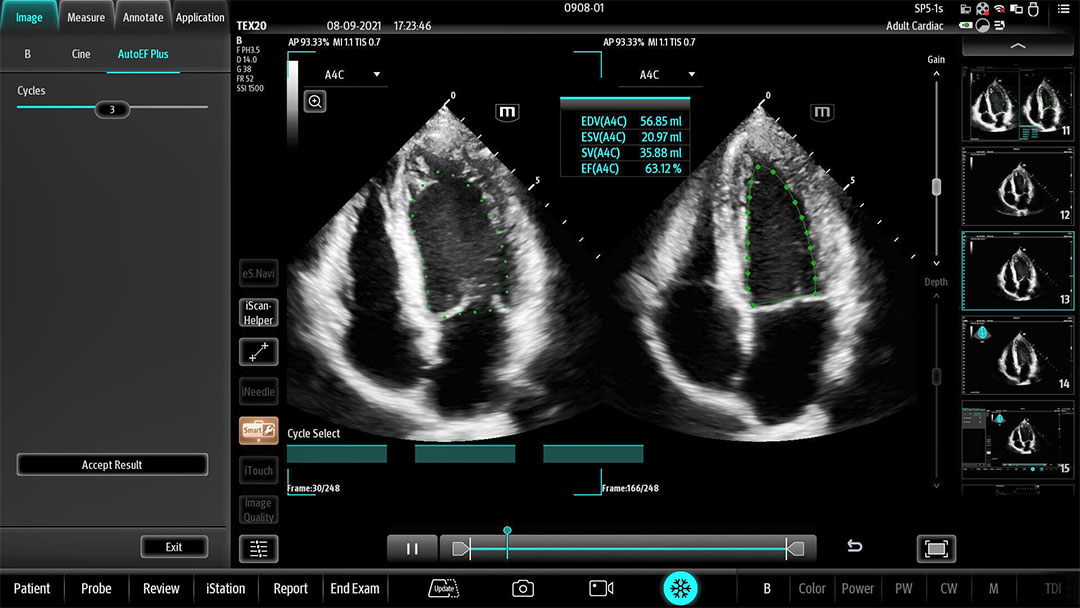

The technology-rich TE X Ultrasound System gives clinicians access to market-leading artificial intelligence (AI)-powered Smart Tools, an ergonomically designed system, and proprietary software-based beamformer Zone Sonography Technology+ (ZST+). By incorporating these elements, the TE X Ultrasound System provides access to advanced diagnostic data, the ability to adapt to the various clinical scenarios at point of care, and best-in-class imaging to help them provide a higher standard of care.